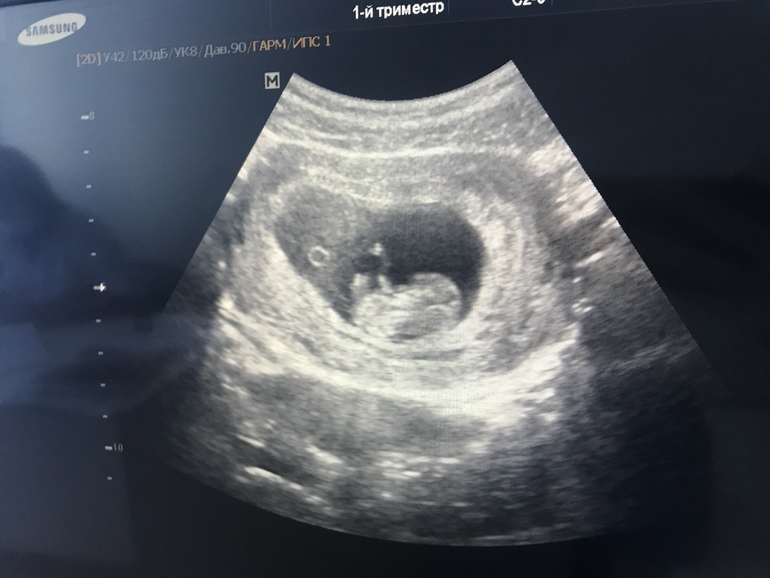

УЗИ, КТГ, доплерНаконец-то я сегодня попала на Узи.

Боже какое же это счастье❤️ По Узи поставили 10+1, по месячным 11+3. Но у меня длинный цикл, овуляция поздняя.

Сказали все хорошо, лежит дёргает ножками, ручками❤️❤️❤️

Сердечко стучит 177 ударов в минуту.

Попросила фото, сказали что не печатаю, но узист предложила лечь ещё раз и сфотографировать на телефон, что я и сделала)